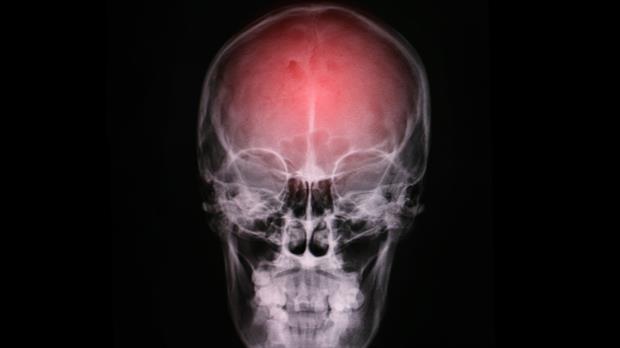

En la Argentina, 15 personas por minuto sufren un infarto cerebral y dos de ellas mueren; consejos para tener un cerebro sano.